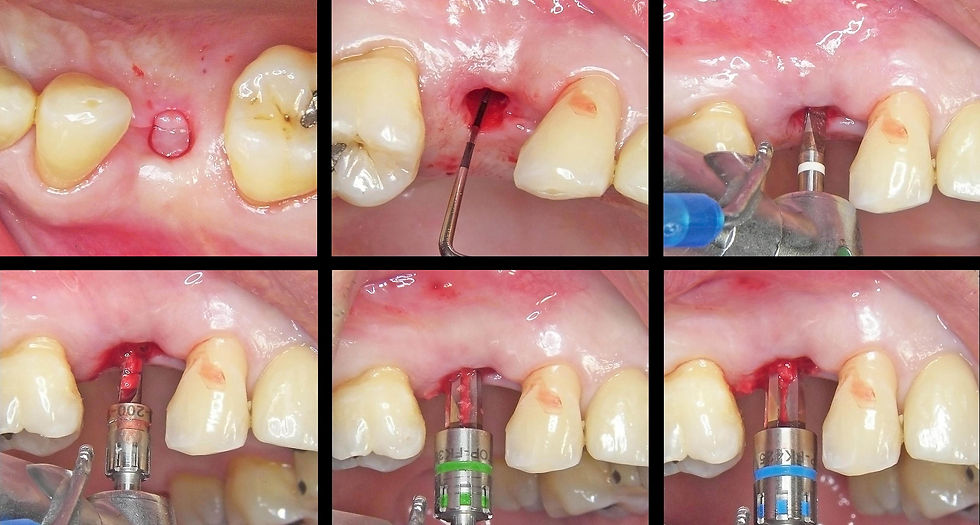

Surgical phases for the delayed flapless insertion of a Prama RF 4.25x13 mm implant with adequate primary stability to proceed with an immediate temporarization.

Insertion of the implant using the Easy Insert driver, which guarantees the preservation of the implant connection.

Insertion of the implant using the Easy Insert driver, which guarantees the preservation of the implant connection. GO TO THE VIDEO